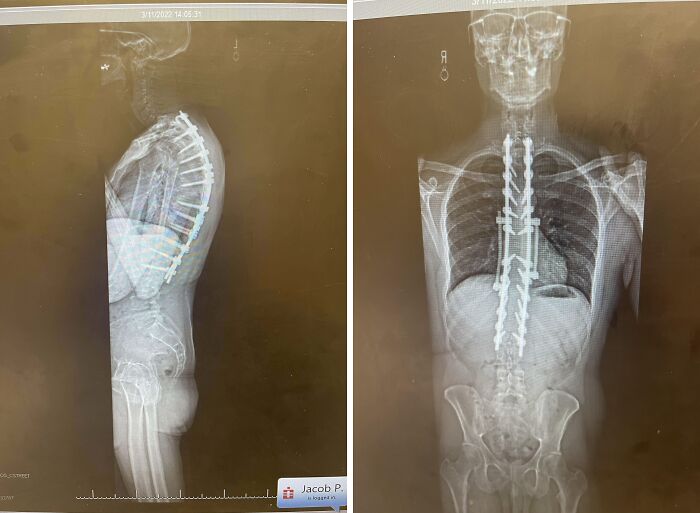

#42 Last September I Had Corrective Surgery On My Back And Now I Have 4 Rods, 22 Screws And 2 Hooks In My Body

Image credits: Nostalgia_Guy80s90s